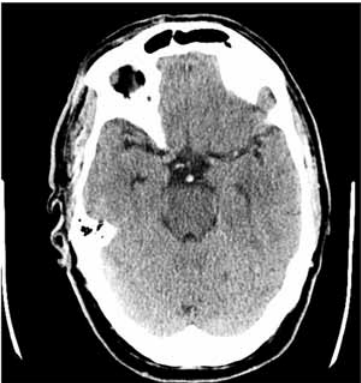

Paciente do sexo masculino, 67 anos, apresentou-se ao hospital com rebaixamento súbito da consciência há uma hora da admissão. Ao exame apresentava tetraparesia flácida, sonolência e nistagmo vertical. Após estabilização hemodinâmica, realizou tomografia de crânio (a seguir). Familiar que acompanha o paciente refere que ele faz uso de medicações para hipertensão arterial e arritmia cardíaca, mas não sabe informar os nomes.

(https://www.google.com/ url?sa=i&url=https%3A%2F%2Fwww.frontiersin.org%)

Assinale a alternativa que apresenta, corretamente, o tratamento mais adequado para esse paciente.